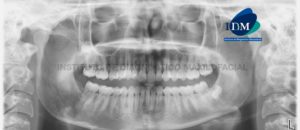

Paciente de 26 años de edad acude al Instituto de Diagnóstico Maxilofacial para evaluación imagenológica de los incisivos superiores. A la evaluación panorámica se evidencio